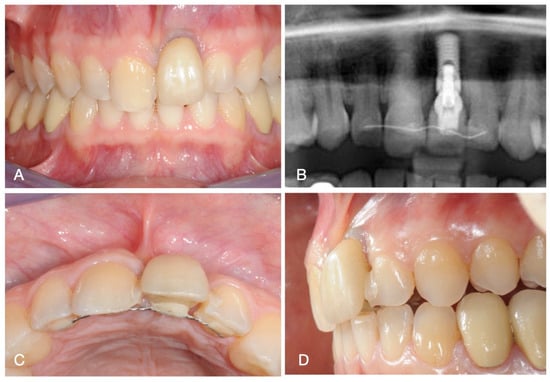

2. Case Report